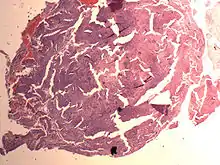

An endometrial stromal nodule is a noncancerous tumor of the uterus.[2]

It is a subtype of endometrial stromal tumor belonging to the mesenchymal tumors of the main body of the uterus.[1] The appearance of the cells is identical to normal endometrial stromal cells.[1] This can only be differentiated from low-grade endometrial stromal sarcoma by confirming lack of infiltration.

The differential includes cellular leiomyoma. Diagnosis may be aided by immunostaining; endometrial stromal nodules are positive for CD10; leiomyomas are positive for caldesmon and desmin (and sometimes CD10).

Endometrial Stromal Nodule